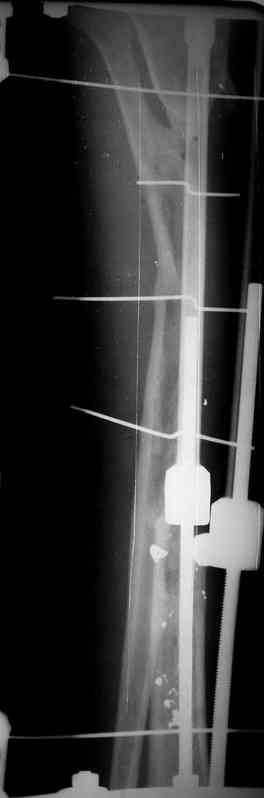

5. Ну и чтобы не быть голословным. Молодой человек подорвался на фугасе (Чечня, 2005 год). Свежие рентгенограммы:

Соответственно ожоги и дефект мягких тканей, переломы костей стопы и пр. Наложили аппарат

Илизарова (как придется), хирургически обработали и героически заживляли мягкие ткани с многочисленными кожными пластиками. В итоге через полгода я принял его вот таким:

Рентген в процессе перемещения - внизу карбоновые кольца, тракция фрагмента спицами с упором.